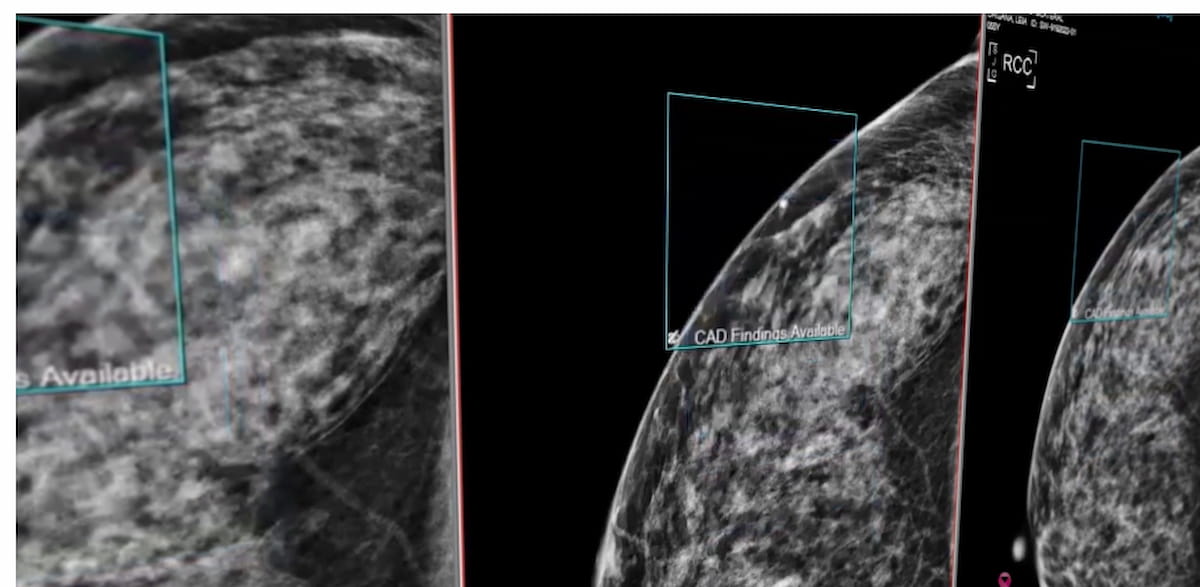

The Breast Suite software reportedly provides automated localization of regions of interest on mammograms as well as AI-enabled assessments of breast density and stratification of breast cancer risk for up to two years.